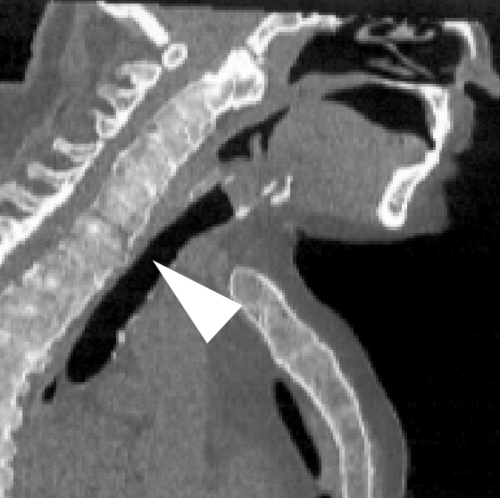

Thoracolumbar compression fracture (T12) with vertebral body height loss, retropulsed fragment, marrow edema, and...

Cone-beam CT phantom of the maxillofacial region showing teeth, alveolar bone, sinuses, nasal cavity, and mandibular...